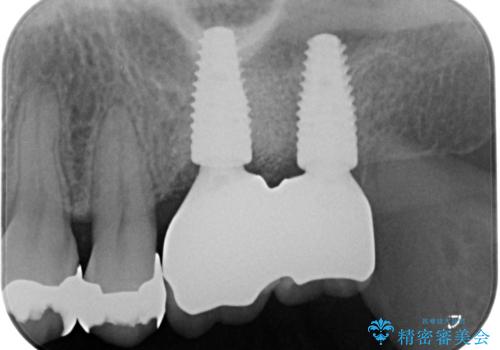

上顎奥歯のインプラント治療

- 奥歯を失い咬合機能の回復のためインプラント治療を希望され来院されました。

奥歯を2本失うと、他の歯の負担が増加し残っている歯の状態が悪くなるリスクがあります。

しっかりと咬合機能の回復できるインプラント治療を計画します。

- 88万円(インプラント×2・チタンカスタムアバットメント×2・ジルコニアクラウン×2・仮歯×2)費用は治療当時の料金となります